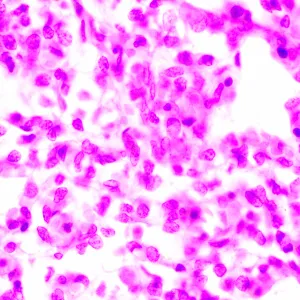

Микроскоп исследовательского класса. Предназначен для наблюдения прозрачных и полупрозрачных биологических образцов в виде мазков и срезов в проходящем свете в светлом поле. Установка опциональных компонентов позволит использовать методы темного поля, фазового контраста, люминесценции и поляризации. Кодированный револьвер сохраняет комфортную яркость при переключении объективов. Интеллектуальное управление освещением микроскопа повышают комфорт, скорость и эффективность работы исследователя. Благодаря «умным» функциям не нужно отвлекаться на настройки, внимание исследователя полностью сфокусировано на решаемых задачах.